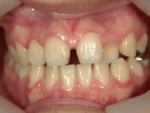

上顎前突(じょうがくぜんとつ)

上の前歯が前へ突き出している状態のことで、いわゆる出っ歯と呼ばれています。前歯の突出によって唇が閉じにくいため口腔内が乾燥しやすく、歯周病や虫歯を誘発しやすくなります。